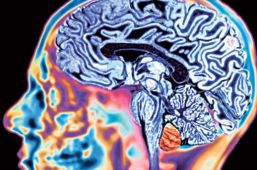

Quienes están más seguros de sus respuestas tienen más células en una pequeña área de sus lóbulos frontales, según un estudio realizado por el University College London (UCL).

A 32 voluntarios se les formuló un cuestionario gráfico difícil y debían responder en qué grado estaban seguros de sus respuestas en una escala de 1 a 6. Quienes estaban más seguros tenían más células cerebrales en la corteza cerebral prefrontal.

La región del lóbulo prefrontal en cuestión está relacionada con enfermedades como el autismo.